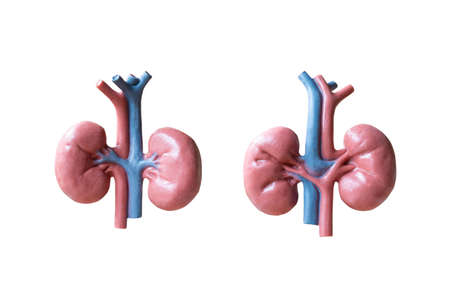

Human Kidneys Anatomical Model isolated on white background

Human Kidneys Anatomical Model isolated on white background